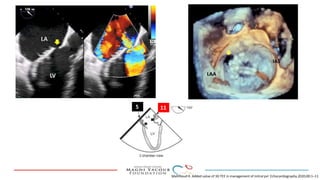

This document provides an overview of percutaneous prosthetic valve leakage (PVL) closure, including indications, approaches, techniques, and closure devices. It discusses that over 210,000 prosthetic valve surgeries are performed each year, with PVL occurring in some cases. While surgical closure has a high mortality rate, percutaneous closure has a procedural success rate of 86% and less complications. Indications for closure include symptomatic heart failure, hemolysis, rocking prosthesis, or leaks over 30% of the sewing ring. Techniques discussed include retrograde and transapical approaches using devices like the Amplatzer and Occlutech plugs. A team approach and techniques like sequential deployment are emphasized for